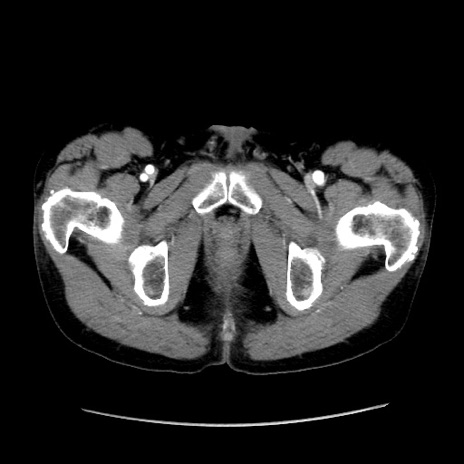

症例37(横断像)

【症例】40歳代 男性

【主訴】腹痛

【現病歴】4時間ほど前に電車に乗車中に臍部上より腹痛出現。徐々に増悪し起立困難となり、救急外来受診。生ものは数日食べていない。今朝お雑煮を食べた。

【身体所見】BT 36.8℃、BP 117/84mmHg、HR 91/min、SpO2 97%、苦悶様、腹部:臍上部広範囲圧痛あり、反跳痛±

【データ】WBC 8100、CRP 0.03